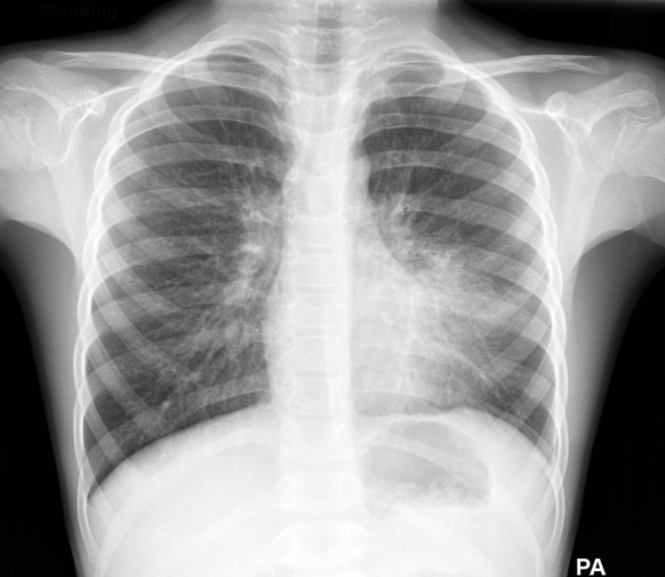

4. 🏥진단은 어떻게 하나요?

병원에서는 증상과 청진 소견 외에도 아래 검사를 시행할 수 있습니다.

- 흉부 X-ray: 폐의 염증 범위 확인